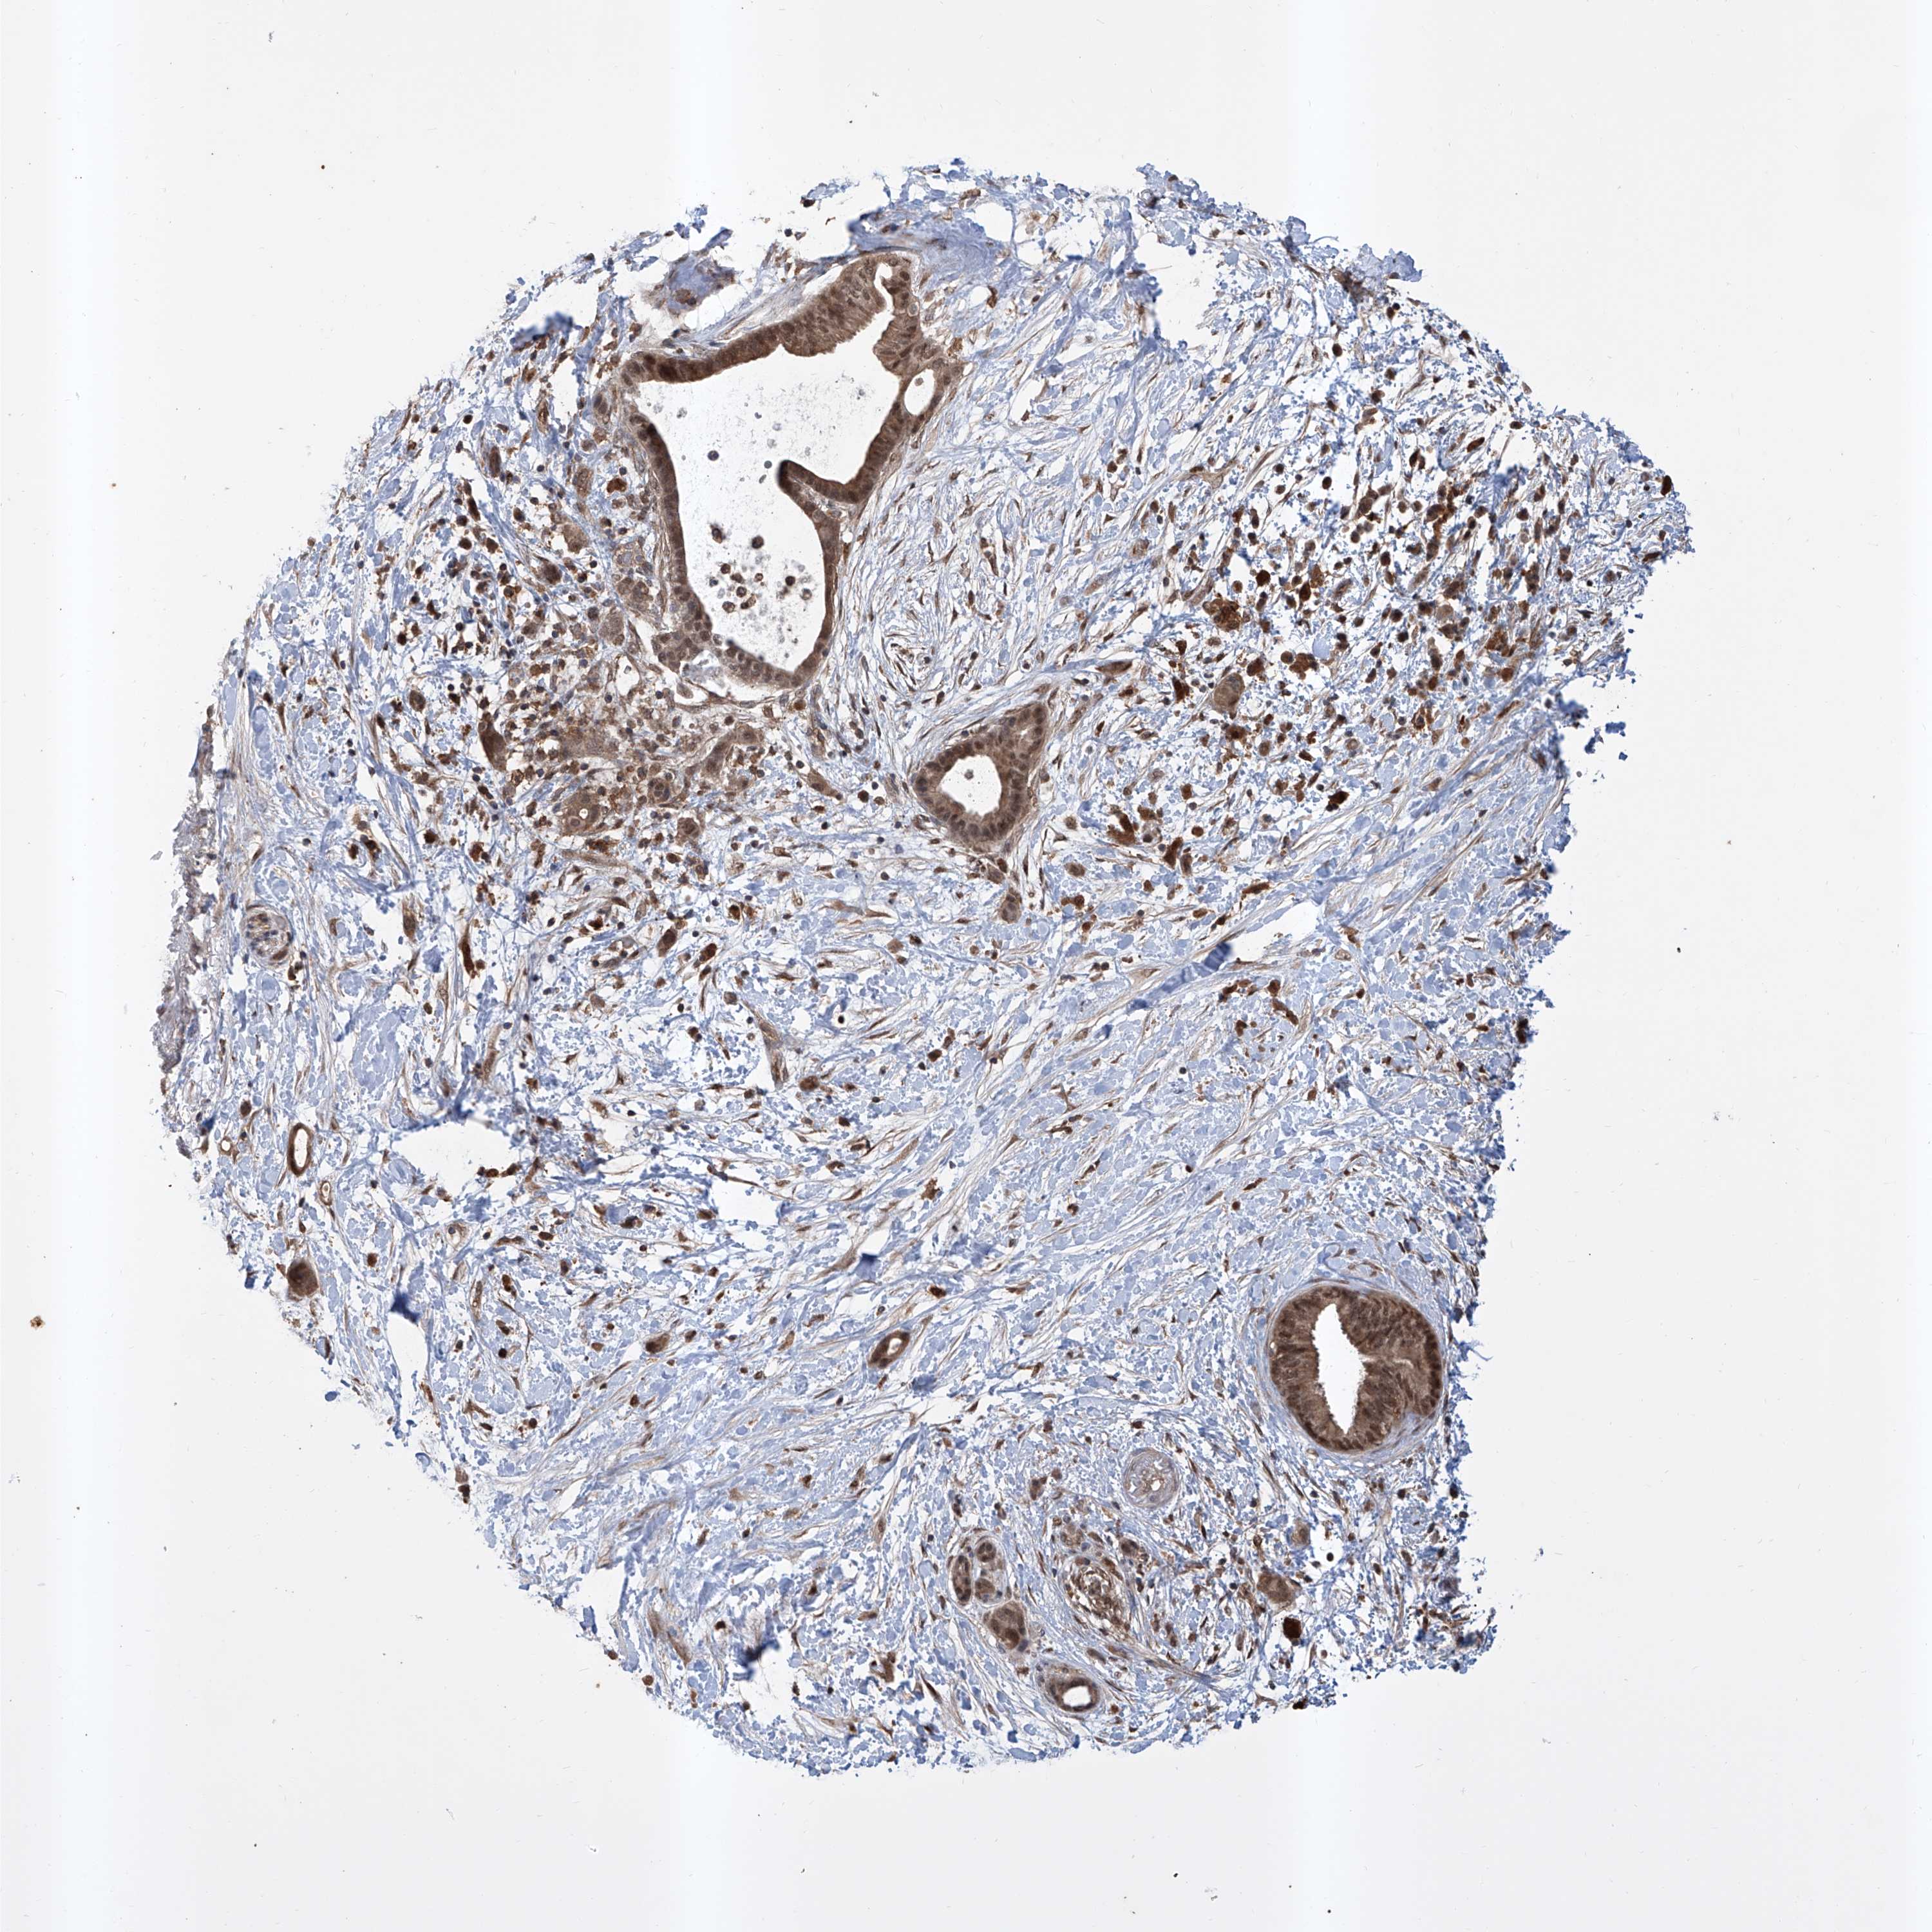

PANCREATIC CANCER - Protein expressioni

A mouse-over function shows sample information and annotation data. Click on an image to view it in a full screen mode. Samples can be filtered based on level of antibody staining by selecting one or several of the following categories: high, medium, low and not detected. The assay and annotation is described here.

Note that samples used for immunohistochemistry by the Human Protein Atlas do not correspond to samples in the TCGA dataset.

Antibody stainingi

Antibody staining in the annotated cell types in the current human tissue is reported as not detected, low, medium, or high, based on conventional immunohistochemistry profiling in selected tissues. This score is based on the combination of the staining intensity and fraction of stained cells.

Each image is clickable and will lead to virtual microscopy that enables deeper exploration of all samples and also displays staining intensity scores, fraction scores and subcellular localization as well as patient and tissue information for each sample.

Antibody HPA028911

Antibody CAB037020

Staining

High

Medium

Low

Not detected

Intensity

Strong

Moderate

Weak

Negative

Quantity

>75%

75%-25%

<25%

None

Location

Nuclear

Cytoplasmic/membranous

Cytoplasmic/membranous,nuclear

Adenocarcinoma, NOS